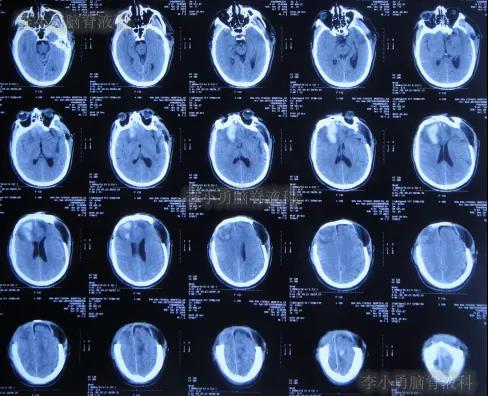

急诊进行了开颅去骨瓣血肿清除术,术后次日查头颅CT示去骨瓣术后(图-2)。

图-2:2019年10月21日头颅CT

图-3:2019年10月22日头颅CT

开颅术后第4天即2019年10月24日,查头颅CT示积血仍未明显减少(图-4)。

图-4:2019年10月24日头颅CT